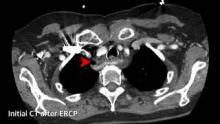

An 82-year-old woman suffered esophageal perforation during attempted endoscopic retrograde cholangiopancreatography (ERCP). Following left transcervical exploration and drainage, the patient remained septic with free perforation into the mediastinum and resulting mediastinitis. This video illustrates endoscopic discovery of perforated Zenker’s diverticulum and endoscopic transnasal drainage of mediastinal abscess.